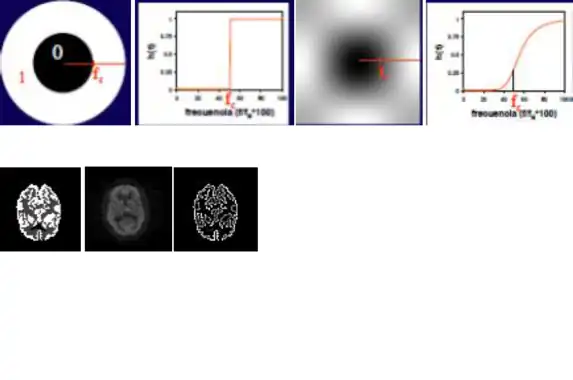

El filtrado las imágenes médicas, en este caso las imágenes de medicina nuclear, pueden asemejar a los filtros paso de banda, debido al estudio de las imágenes en el espacio de las frecuencias (espacio de Fourier).

Filtros paso-baja

Este filtro efectúa un filtrado paso-baja cuyo grado de filtrado se controla por el radio del círculo. Un filtro muy abrupto puede producir oscilaciones en la imagen (fenómeno de Gibbs) por lo que suelen emplearse filtros paso-baja como el indicado a la derecha, que tienen una variación más suave. Son filtros con valores altos en el origen y que se atenúan hacia altas frecuencias.

Un filtro paso-baja puede implementarse también en el dominio espacial mediante convolución con una máscara de filtrado. La implementación de este filtro en el dominio espacial presenta ventajas en tiempo de cálculo frente a una implementación en el dominio frecuencial. Como regla general, si la respuesta impulsional del filtro es de tamaño menor que 12x12 píxels, el filtrado es mejor realizarlo en el dominio especial.

El radio del círculo, que determina el grado de filtrado, se expresa como fracción de la frecuencia de Nysquist.

Filtro paso-alta

La implementación de un filtro paso-alta puede realizarse en el espacio de Fourier, con un planteamiento complementario al del filtro paso-baja.

El efecto de este filtro, que actúa por multiplicación en el espacio de Fourier será, pues, de potenciación de la alta frecuencia y eliminación de la baja frecuencia. Son filtros de realce o de extracción de contornos.

Un ejemplo de filtro paso de alta es el filtro laplaciano, el cual es omnidireccional y extrae contornos en todas direcciones.

Con este tipo de filtros, la detección del contorno es perfecta en las imágenes sintéticas sin ruido, pero en la imagen con ruido del estudio real, el filtro no sólo no detecta el contorno sino que potencia el ruido. Este refuerzo del ruido es una característica de los filtros paso-alta.

El grado de filtrado se controla con el radio del círculo interior, que controla la frecuencia de corte.